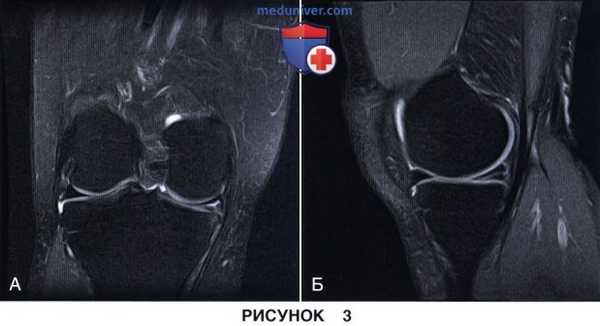

• Горизонтальный разрыв по типу расслоения мениска:

- На рис. 3 представлены фронтальный (рис. 3, А) и сагиттальный (рис. 3, Б) МР-срезы с признаками горизонтального разрыва заднего рога внутреннего мениска